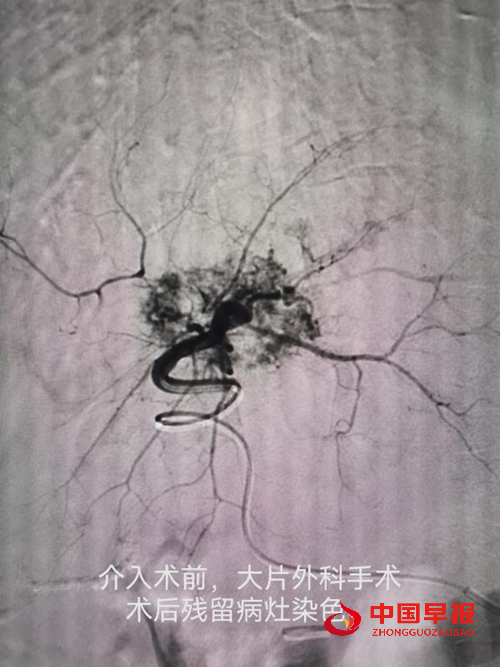

病例一:刘先生,男,55岁,患肺癌,经过三次介入微创手术+三次细胞治疗+靶向治疗,肺癌缩小90%,全身脊柱转移灶得到控制硬化,全身剧痛消失,处于NED状态。